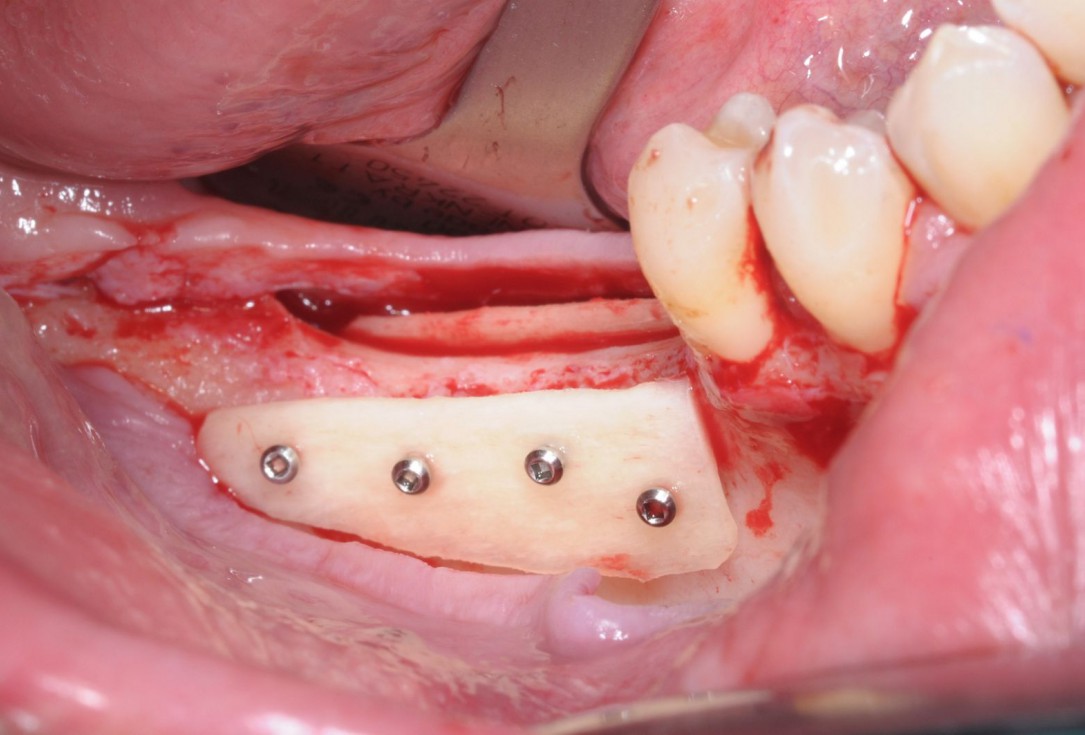

06/28 - Fixation of two defect-adapted maxgraft® cortico plates with osteosynthesis screwsThree-dimensional augmentation with maxgraft® cortico - Dr. R. Würdinger